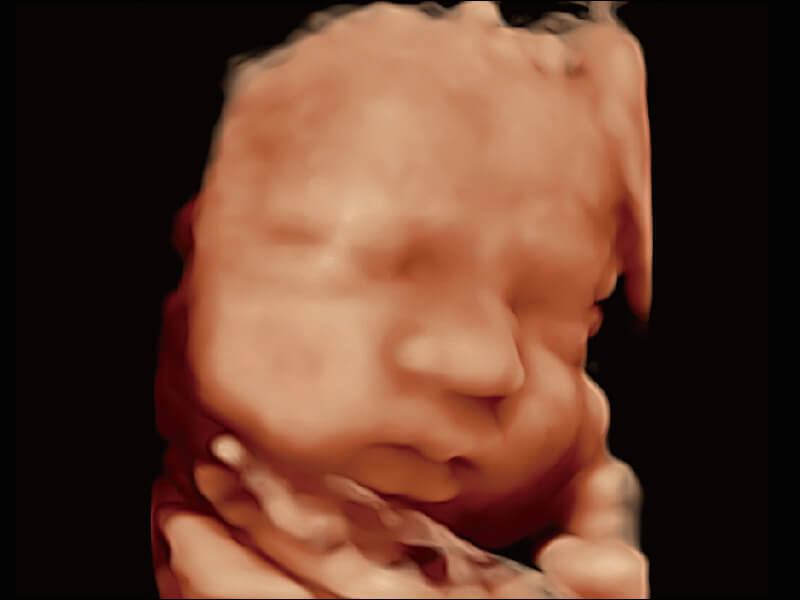

S60探头工艺,从前端信号处理每一个环节采集无损声学数据,真实还原组织原貌,再现解剖细节。

超宽频带技术,为容积成像带来优质的二维图像基础,为您呈现丰富的结构细节,栩栩如生地展示宝宝的宫内形态以及各种组织的立体结构。